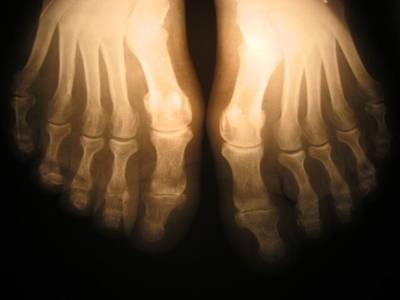

• рентгенографию;